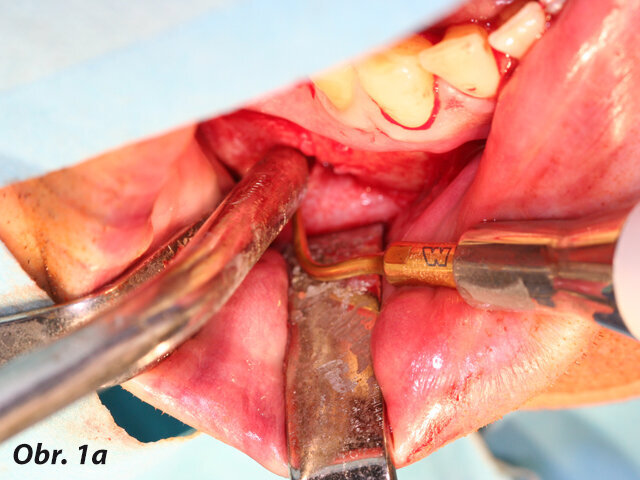

Při výkonech dentoalveolární chirurgie používáme koncovky osteoplastické, jejichž pomocí lze šetrně odpreparovat kostní tkáň nad retinovanými zuby ať v případě jejich následující extrakce nebo v případě následné fenestrace či tunelizace, kdy je možné jejich následné ortodontické zařazení do zubního oblouku.

Opatrnost doporučujeme při preparaci v blízkosti skloviny – pokud totiž dojde k přímému kontaktu piezochirurgické koncovky se sklovinou zubu, nelze vyloučit rozvoj mikrofraktur skloviny, která má odlišné mechanické vlastnosti než kost.

Osteotomické koncovky používáme pouze k separaci zubních tkání, které budeme závěrem extrahovat. S výhodou pro situace, kdy plánujeme okamžitou implantaci, je provedení extrakce pomocí piezochirurgie, ne však způsobem, který je často demonstrován na různých školeních a workshopech. Tam bývá stomatologům často doporučováno použití extrakční koncovky místo periotomu. To může vést k přehřátí okolní kosti a následným komplikacím ve smyslu alveolitis sicca. Extrakce v těchto situacích by měla být provedena jako postupná separace kořene a jeho odstranění po částech, přičemž okolní kostní tkáně se snažíme dotýkat minimálně, abychom nepoškodili kostní buňky zubního lůžka.